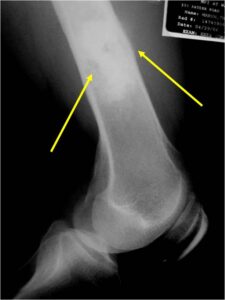

Radiology emulates pathology: Biphasic Tumor

- One region low grade chondrosarcoma

- Second more aggressive area with bone destruction, lysis of calcification, soft tissue mass

Ill-defined, lytic intraosseous lesion

- Devoid of calcifications in continuity with lesions having the features of a cartilaginous tumor

Characteristically abrupt transition between chondroid tumor and dedifferentiated, lytic component

Bone may be expanded and adjacent cortex thickened